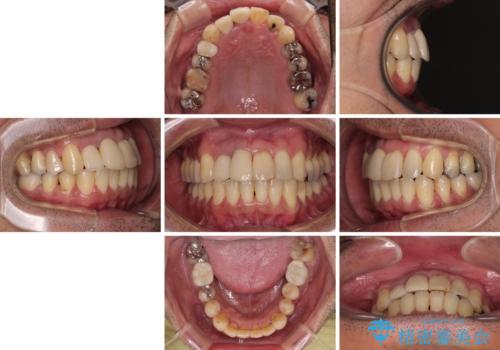

隠れている前歯 インビザライン矯正治療と前歯のセラミック治療

矯正治療後は、前歯や下顎の奥歯など、むし歯治療途中の歯をオールセラミッククラウンにて補綴治療を行うこととしました。

治療途中で海外に長期滞在することとなり、5年近く帰国することができなかったため、治療期間は非常に長いものとなりました。

内側に転位していた前歯は、矯正治療では治しきることができませんでしたが、幸いにもオールセラミッククラウンに置き換える予定であったため、希望通りの仕上がりとなりました。